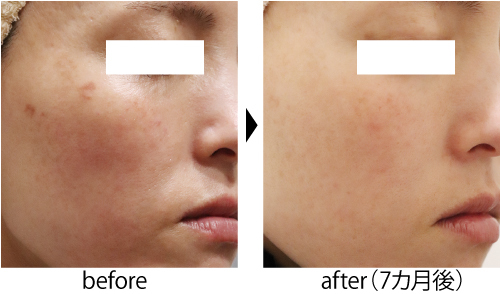

炎症後色素沈着の治療を皮膚科専門医が症例写真で解説うらた皮膚科。

☆背中の色素沈着治療~症例写真セイコメディカルビューティクリニック鹿児島福岡。

頑固な色素沈着、いつ消える?👨🏻⚕️顔や体にできる色素沈着、時間が経ってもなかなか消えない💦ということはありませんか?今回はさまざまなタイプの色素沈着に有効な治療や おすすめのホームケアをまとめました🙆♂️ 当院での症例も載せています✍️ よく色素。

症例集きずときずあとのクリニック色素沈着の治療についてきずときずあとのクリニックきずときずあとのクリニック豊洲院きずときずあとのクリニック銀座院形成外科美容外科美容皮膚科症例傷跡傷跡修正傷跡治療きずクリ症例集色素沈着q。

肝斑、炎症後色素沈着治療の症例写真横浜・桜木町の テティス横濱美容皮膚科。

赤み・色素沈着症例紹介ニキビ跡のクレーター・毛穴でお悩みの方へ「花房式ニキビ跡治療」。

シミのレーザー治療後の経過・炎症後色素沈着を検証してみたBeauty Tuning Clinic。

レーザー後の色素沈着例 ちゃんと改善クララビューティクリニック那覇院。